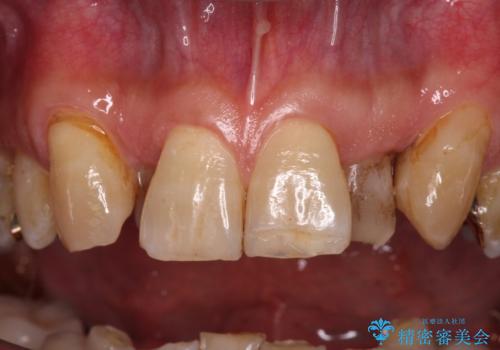

- 下顎両側の欠損と上顎前歯のデコボコを気にして来院された患者様です。

デコボコは今まで気にせずにいたそうですが、奥歯の欠損改善を機に、矯正治療に興味があるので、相談したいとのことでした。

奥歯に欠損が多く、矯正治療はやや難航することが予想されますが、患者様の希望もあり、上顎左右小臼歯を1本ずつ抜歯し、ワイヤー装置にて矯正治療を行うこととしました。

矯正歯科治療を行うに当たり、痛みや違和感を感じている歯の根管治療を行い、矯正治療中にインプラント埋入し、補綴治療と矯正治療を同時に終了できるように進めて行くこととしました。